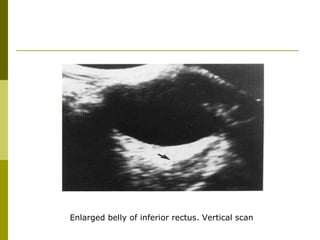

Enlarged belly of inferior rectus. Vertical scan

Enlarged belly ofinferior rectus. Vertical scan